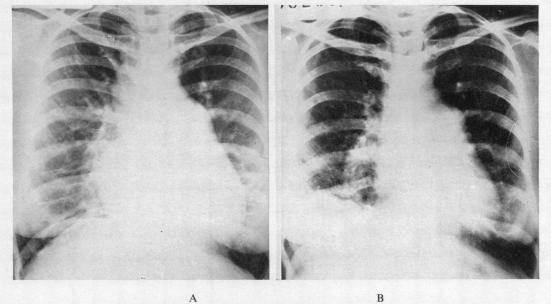

HICKIE J B, GIMLETTE T M, BACON A P

Br Heart J. 1956 Jul;18(3):365-77. doi: 10.1136/hrt.18.3.365.